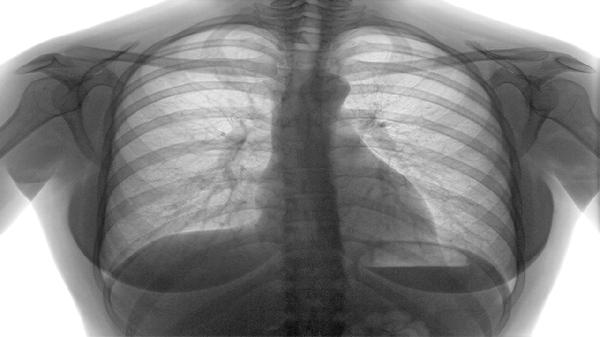

肺结核患者应保证充足营养摄入,每日蛋白质摄入量不低于1.5克每公斤体重,可适量增加牛奶、鸡蛋、瘦肉等优质蛋白食物。同时需注意休息,避免劳累,保持居住环境通风良好。严格遵医嘱完成6-9个月规范治疗,不可随意中断用药,定期复查胸部影像学和痰菌检测。出现药物不良反应时应及时就医调整方案,治疗期间需隔离痰菌阳性患者,佩戴口罩并妥善处理痰液。